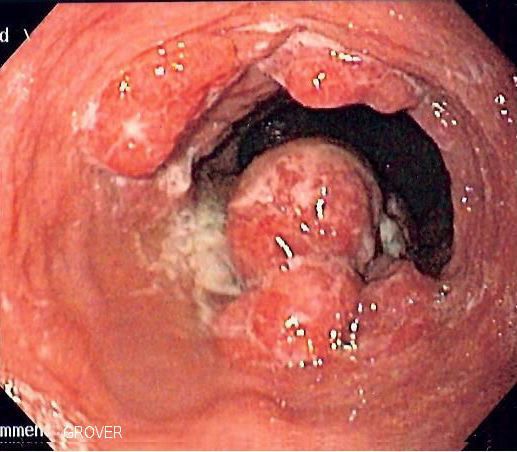

Esophageal cancer

Oesophageal cancer is a type of cancer affecting the oesophagus (gullet) – the long tube that carries food from the throat to the stomach. It mainly affects people in their 60s and 70s and is more common in men than women.